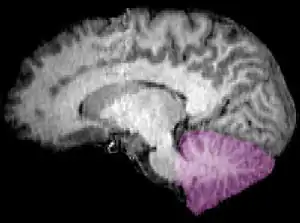

![]() Cerebelo en púrpura. Sección sagital de un encéfalo en una RMN. | ||